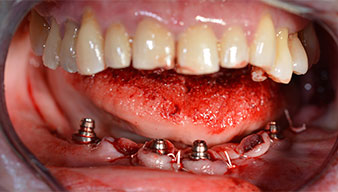

Um die Divergenz der distalen Implantate auszugleichen, werden abgewinkelte Abutments (35 Grad) eingeschraubt, sodass die Austrittsprofile sämtlicher Implantate möglichst senkrecht zur Kauebene stehen. Dies ist Voraussetzung, um die provisorische und später auch die endgültige Versorgung okklusal verschrauben zu können (Abb. 15 und 16).

Im Anschluss erfolgt die Abformung und Bissnahme, sodass die Zahntechniker umgehend mit der Anfertigung der provisorischen Arbeit beginnen können. Diese wird im Anschluss am gleichen Tag eingeschraubt (Abb. 17 und 18).